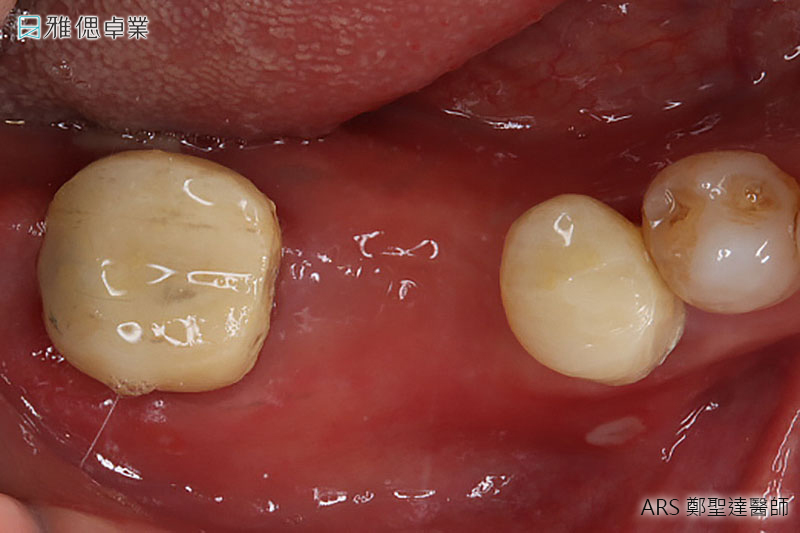

STEP3 牙齦塑形

植體在人體內3個月後,骨整合已經足夠支持咬合力,為了塑造未來牙套的牙齦型態,醫師會在植體上端接入牙齦成形帽,使牙齦生長為理想形狀。

STEP4 取得牙套(假牙)主要模型

醫師會為您的植體設計客製化的支台齒(連結人工植牙與假牙),來支撐牙套,並且會為您和原本的牙齒進行比色,讓患者植牙完成時,假牙顏色不會和真牙顏色有所落差。